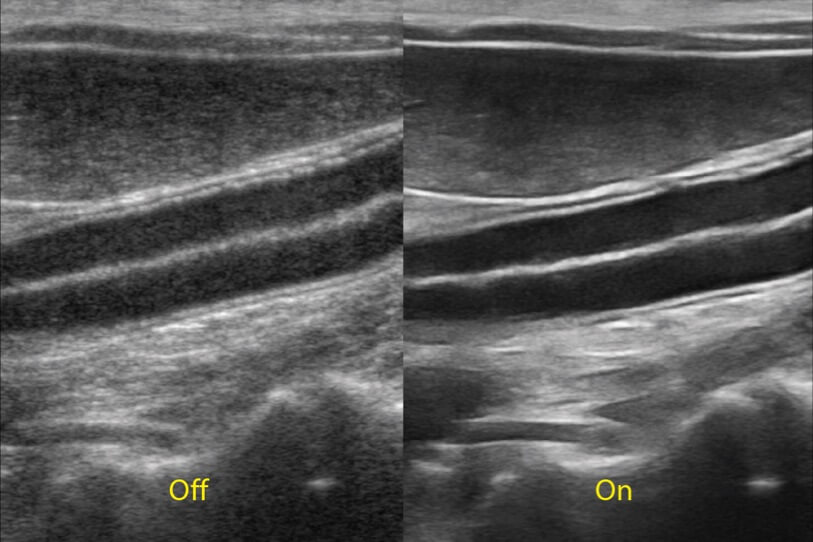

ProPet 70 进一步提升了微米成像算法,更加注重对基础原始图像的还原和保留,在有效减少斑点噪声、增强组织边界显示的同时,避免过度优化丟失真实的解剖信息。